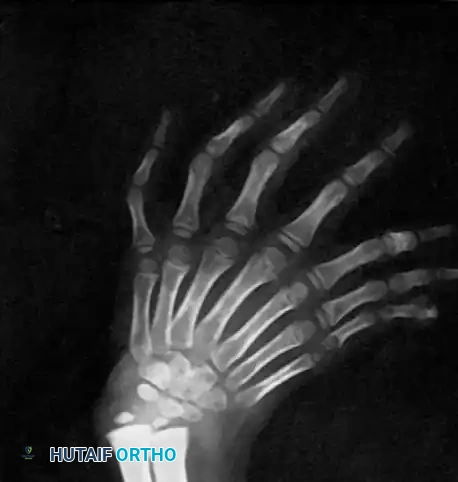

TRIPHALANGEAL THUMB

A triphalangeal thumb is defined by the presence of three phalanges instead of the normal two. This rare anomaly is frequently inherited as an autosomal dominant trait and has historical associations with maternal thalidomide exposure.

Triphalangeal thumbs frequently coexist with other congenital anomalies, including cleft foot, tibial hemimelia, congenital heart disease, and gastrointestinal malformations.

Radiograph demonstrating a triphalangeal thumb with a distinct extra phalanx interposed between the proximal and distal phalanges.

Pathoanatomy and Classification

Triphalangeal thumbs are broadly categorized into two major morphological types based on the shape of the extra ossicle:

1. Type I (Delta Phalanx / Wedge-Shaped Ossicle):

The extra phalanx is small and wedge-shaped (a delta phalanx with a longitudinally bracketed epiphysis). This asymmetrical growth plate causes a progressive, severe angular deformity (clinodactyly) without significantly increasing the overall length of the thumb. The thumb is typically deviated ulnarward at the interphalangeal joint level.

2. Type II (Five-Fingered Hand / Rectangular Phalanx):

The extra phalanx is rectangular and nearly normal in appearance, creating the illusion of a five-fingered hand. The thumb is abnormally long and lies in the same plane as the other digits (loss of pronation).